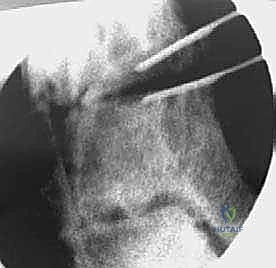

3. إجراء القطع العظمي (Osteotomy)

باستخدام أدوات قطع عظمية دقيقة جداً (مناشير جراحية متأرجحة)، وتحت توجيه جهاز الأشعة السينية المباشر في غرفة العمليات (C-arm)، يتم إحداث القطع في عظم الظنبوب في المكان المخطط له مسبقاً، مع الحفاظ على جزء بسيط من القشرة العظمية في الجهة المقابلة لتعمل كمفصلة (Hinge).